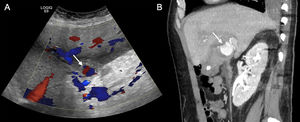

Ultrasound is the first choice in peripheral artery pseudoaneurysms because of its accessibility,2 as well as in paediatric patients, pregnant women and patients with renal failure. On ultrasound (B-mode), the pseudoaneurysm appears as an anechoic structure connected to the artery it arises from by a neck. The neck shows antegrade flow during systole and retrograde flow during diastole, referred to in the literature as "to-and-fro". On colour Doppler ultrasound, this translates into turbulent flow in the non-thrombosed portion of the pseudoaneurysm, where the characteristic "yin-yang" sign is sometimes seen.3,5 In the pulsed Doppler study, where flows and curves are evaluated, a bidirectional flow curve is detected (Fig. 1).

81-year-old man presenting with a pulsatile left inguinal tumour-like lesion at the puncture site with haematoma extending to the root of the thigh after transfemoral catheterisation eight days prior. Colour (A) and spectral (B) Doppler ultrasound images showing a pseudoaneurysm with turbulent flow and the "yin-yang" sign inside the sac (arrow) connecting to the left superficial femoral artery via a neck (arrowhead). Spectral Doppler reveals the bidirectional arterial flow characteristic of pseudoaneurysm.